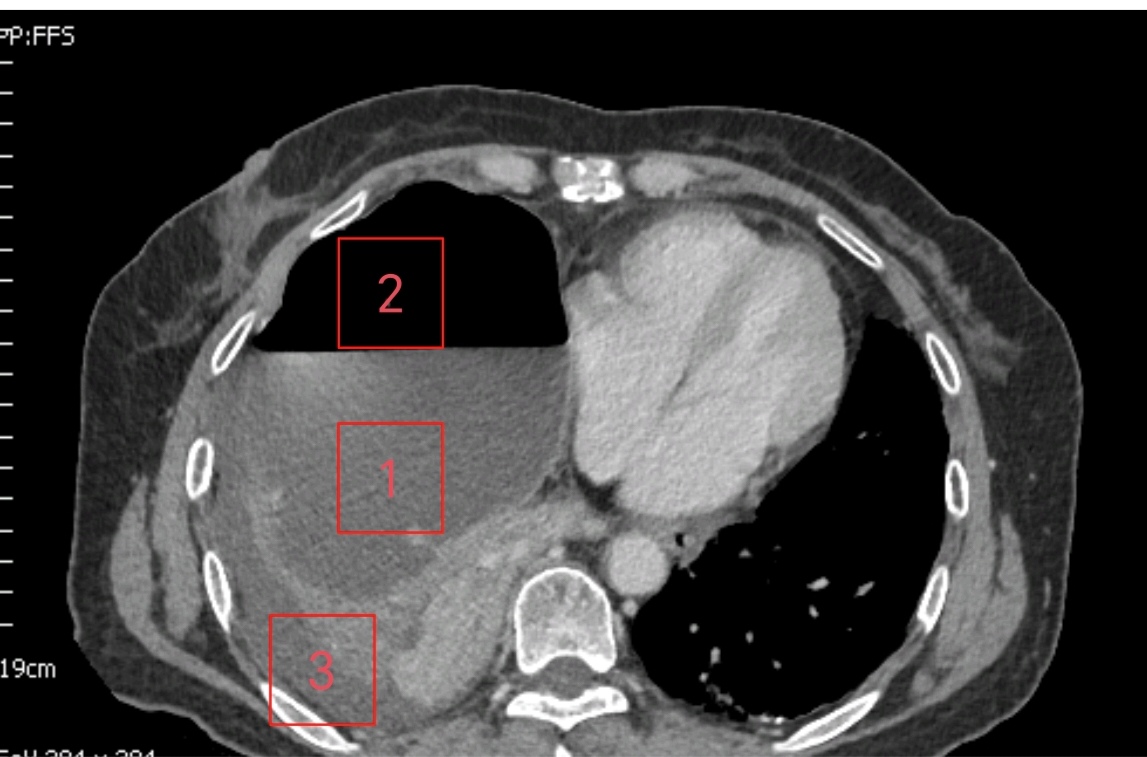

▲闭式引流前

▲闭式引流后